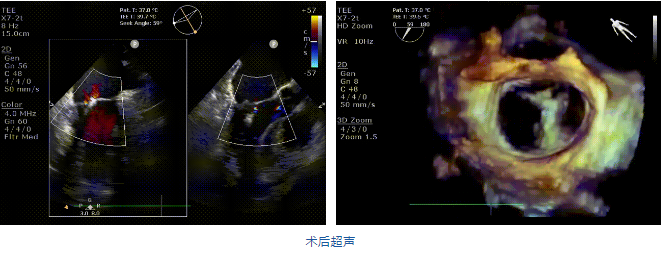

近日,海軍軍醫(yī)大學(xué)長(zhǎng)海醫(yī)院心外科韓林教授團(tuán)隊(duì)在中國(guó)醫(yī)學(xué)科學(xué)院北京阜外醫(yī)院/云南省阜外心血管病醫(yī)院潘湘斌教授團(tuán)隊(duì)的支持下成功應(yīng)用我國(guó)創(chuàng)新器械JensClip為一例二尖瓣重度反流患者開展二尖瓣緣對(duì)緣修復(fù)手術(shù)。在韓林教授團(tuán)隊(duì)的密切配合下,手術(shù)圓滿完成,患者重獲“心”生。術(shù)后即刻超聲顯示二尖瓣反流顯著改善,術(shù)畢即刻拔管,患者恢復(fù)良好。

在阜外醫(yī)院潘湘斌教授團(tuán)隊(duì)的支持下,手術(shù)經(jīng)股靜脈-房間隔入路,采用全身麻醉插管,在TEE和DSA引導(dǎo)下完成房間隔穿刺。置入JensClip瓣膜夾系統(tǒng)后,在左房調(diào)整瓣膜夾的位置和軸向,后進(jìn)入左室,在TEE引導(dǎo)下捕捉二尖瓣前后瓣葉,并關(guān)閉瓣膜夾。經(jīng)TEE反復(fù)確認(rèn)手術(shù)效果后最終鎖定并釋放瓣膜夾。術(shù)后即刻超聲顯示瓣膜夾位置穩(wěn)定,功能良好,二尖瓣反流由術(shù)前4+減少至微量,手術(shù)圓滿成功。